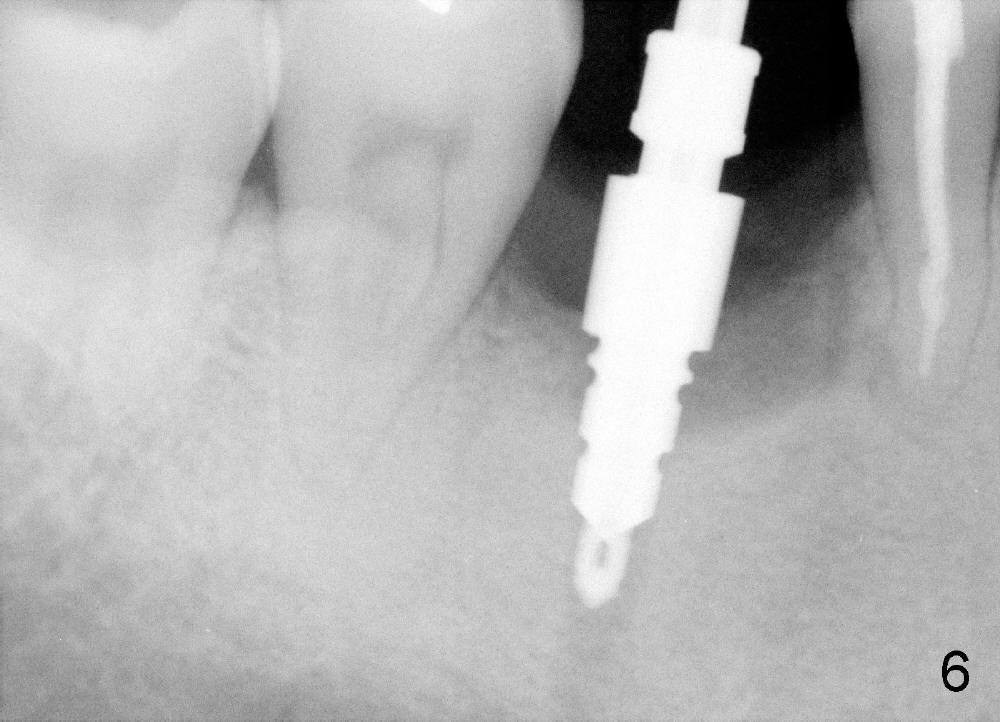

A 46-year-old man has severe periodontitis. The tooth #30 is complicated by incomplete root canal therapy (Fig.1,2). Three months after extraction (Fig.3-5: N: inferior alveolar canal), a 5x14 Tatum tapered implant is placed (Fig.6,7). The problem is that an implant driver is fractured (D in Fig.7), while the implant is being torqued. It takes time and effort to remove the fractured driver, but the implant is solid. The healing screw is placed without difficulty (Fig.8). Since the implant is placed lower than the lingual gingiva (L in Fig.9), a healing cuff is placed 1.5 months after implant placement (Fig. 10 and 11: C) to push the lingual gingiva down. The X-ray appears to show lower bone density around the implant (bone necrosis?), although the implant has no mobility at all. Since the implant is so solid, can we load it, two months after surgery? The lingual gingiva is now lower than the healing cuff (not shown). CT is scheduled to be taken tomorrow. Thanks.

I would load now, but allow a

provisional(acrylic) crown to remain in place another month before placing the

final crown. Make sure the provisional has NO lateral contacts in function. When

removing the broken "driver" be sure to use copious coolant. Make sure the crown

has its margin on the implant ! Dr B